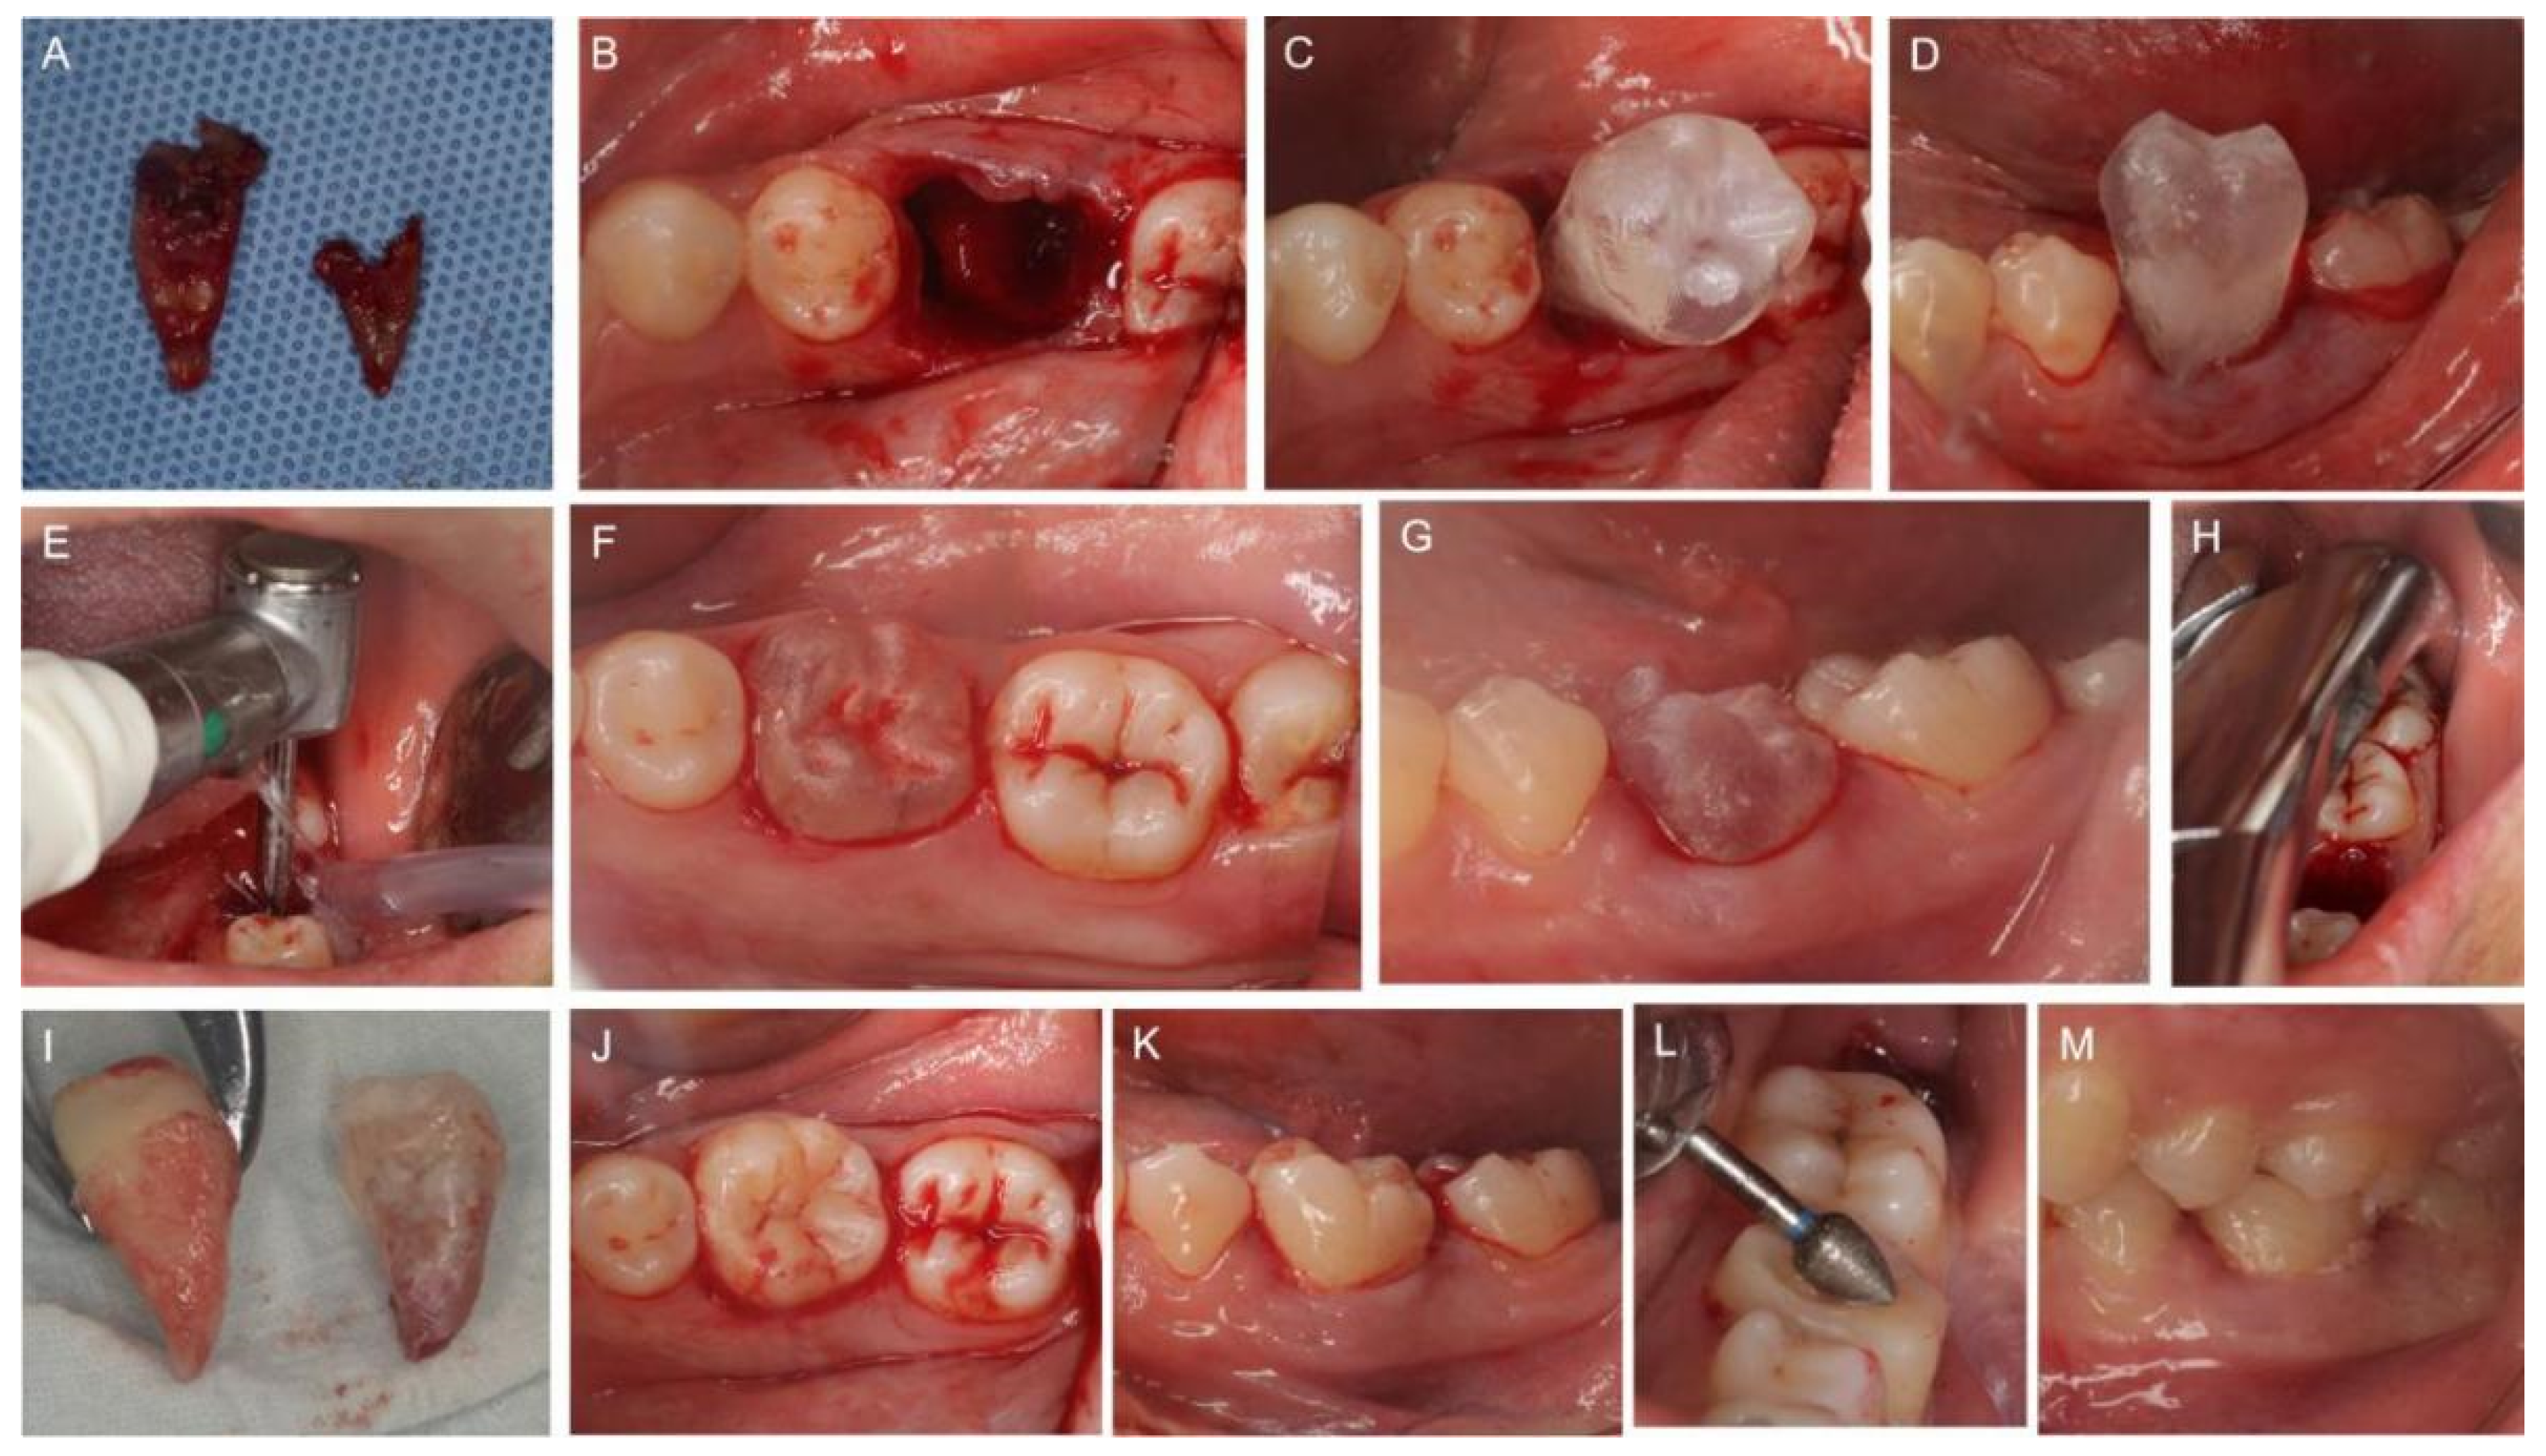

2. Case Report

2.3. Clinical Procedures